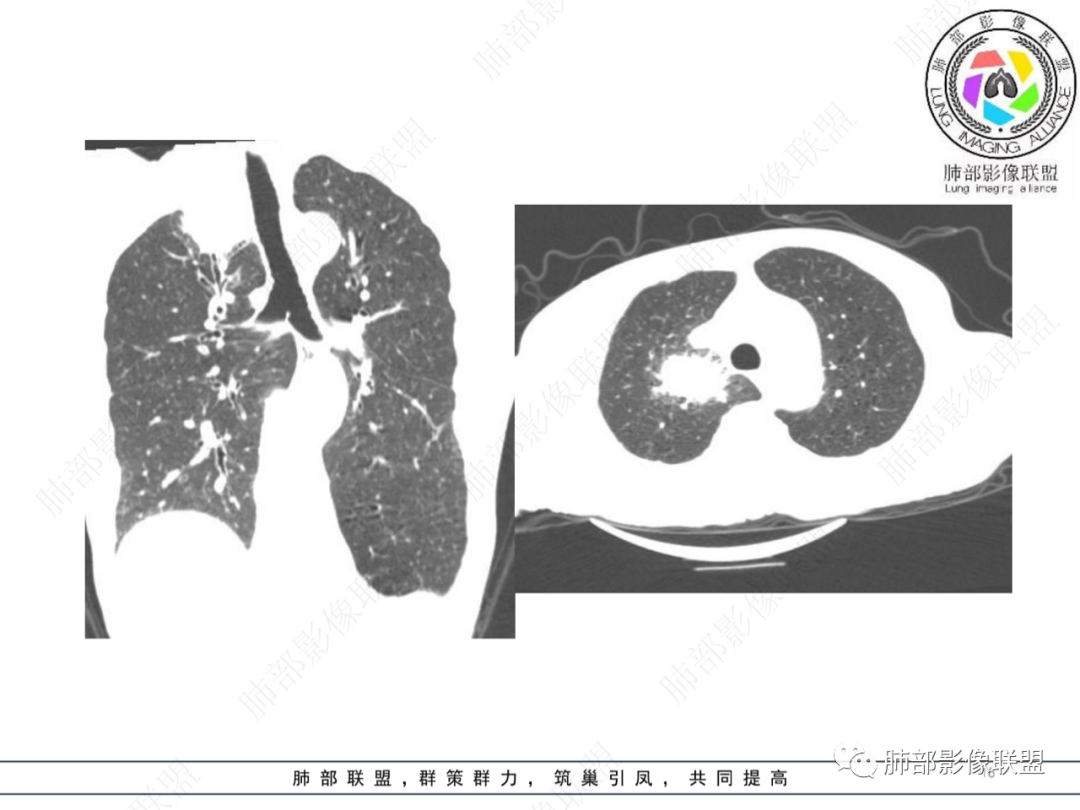

1月后,发热再次入院

这些新发的

合并有胸水

出现液气平面

治疗一周后复查

周围干净了,液平小了

壁似乎均匀了

治疗两周,病灶内气体没了

就目测看内壁还是清楚的

患者有高血压、脑梗死、肾结石病史,因左胸痛不适入院,伴高热,血常规示白细胞、中性粒细胞高。胸部CT示右肺上叶肿块影,边缘模糊影,内可见低密度坏死,边界清楚,一月后出现气液平面,周围渗出,治疗2周复查液平及周围炎症吸收,肿块未见明显吸收。